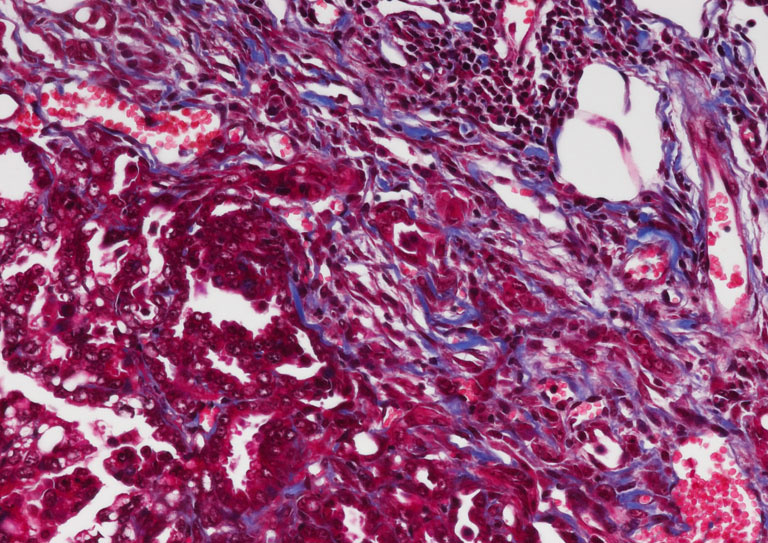

"This image shows a lung adenocarcinoma with a large stromal infiltration. I took the image to show that there is a large stromal infiltration present in lung tumors. Whether this stroma is actively contributing to tumorigenesis is a question I am addressing in my project.

Our understanding of the role of the tumor microenvironment in the development and progression of lung cancer, the most common type of cancer worldwide, remains rudimentary. The goal of my project is to determine whether the stroma contributes to tumor progression as insights into the complex, reciprocal interactions between tumor and stromal cells in their local surroundings may provide new opportunities for more focused therapeutic strategies."